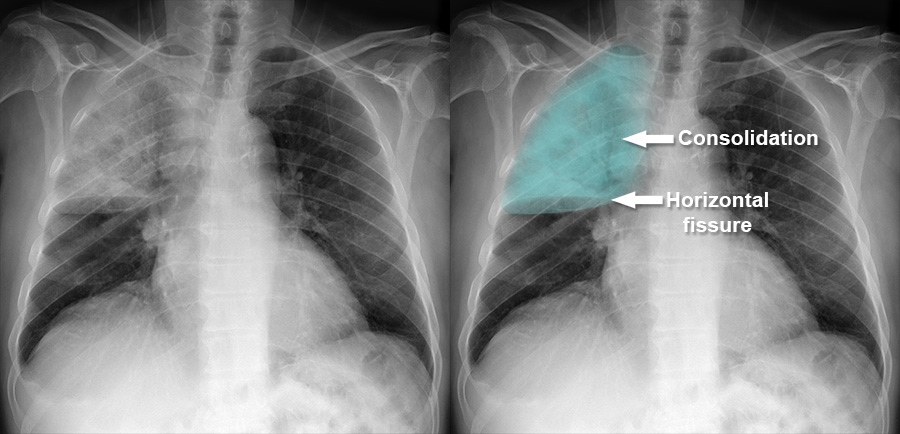

Lobar Pneumonia Xray

Chest X Ray Consolidation

Rt Lower Lobe Pneumonia